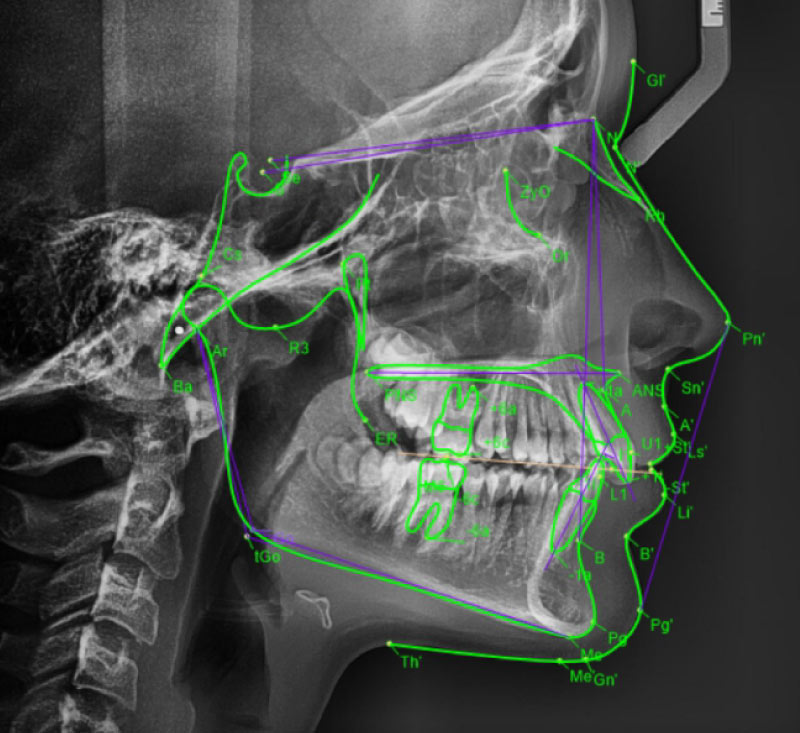

Lateralni kefalogram

Telerendgen ili profilni snimak koji se najčešće koristi pri postavljanju ortodontske dijagnoze i pravljenju plana terapije, ali i kao kontrolni snimak u toku i po završetku ortodontskog tretmana. Na njemu se vidi koštani profil glave i konture mekih tkiva profila lica.Na ovom snimku ortodonti rade kefalometrijska merenja (kefalometriju), a na osnovu njih i različite analize (kefalometrijske analize).

KEFALOMETRIJSKE ANALIZE

Kefalometrijske analize se podižu na OrtoCloud server u 48 časova od snimanja (najčešće u istom danu)